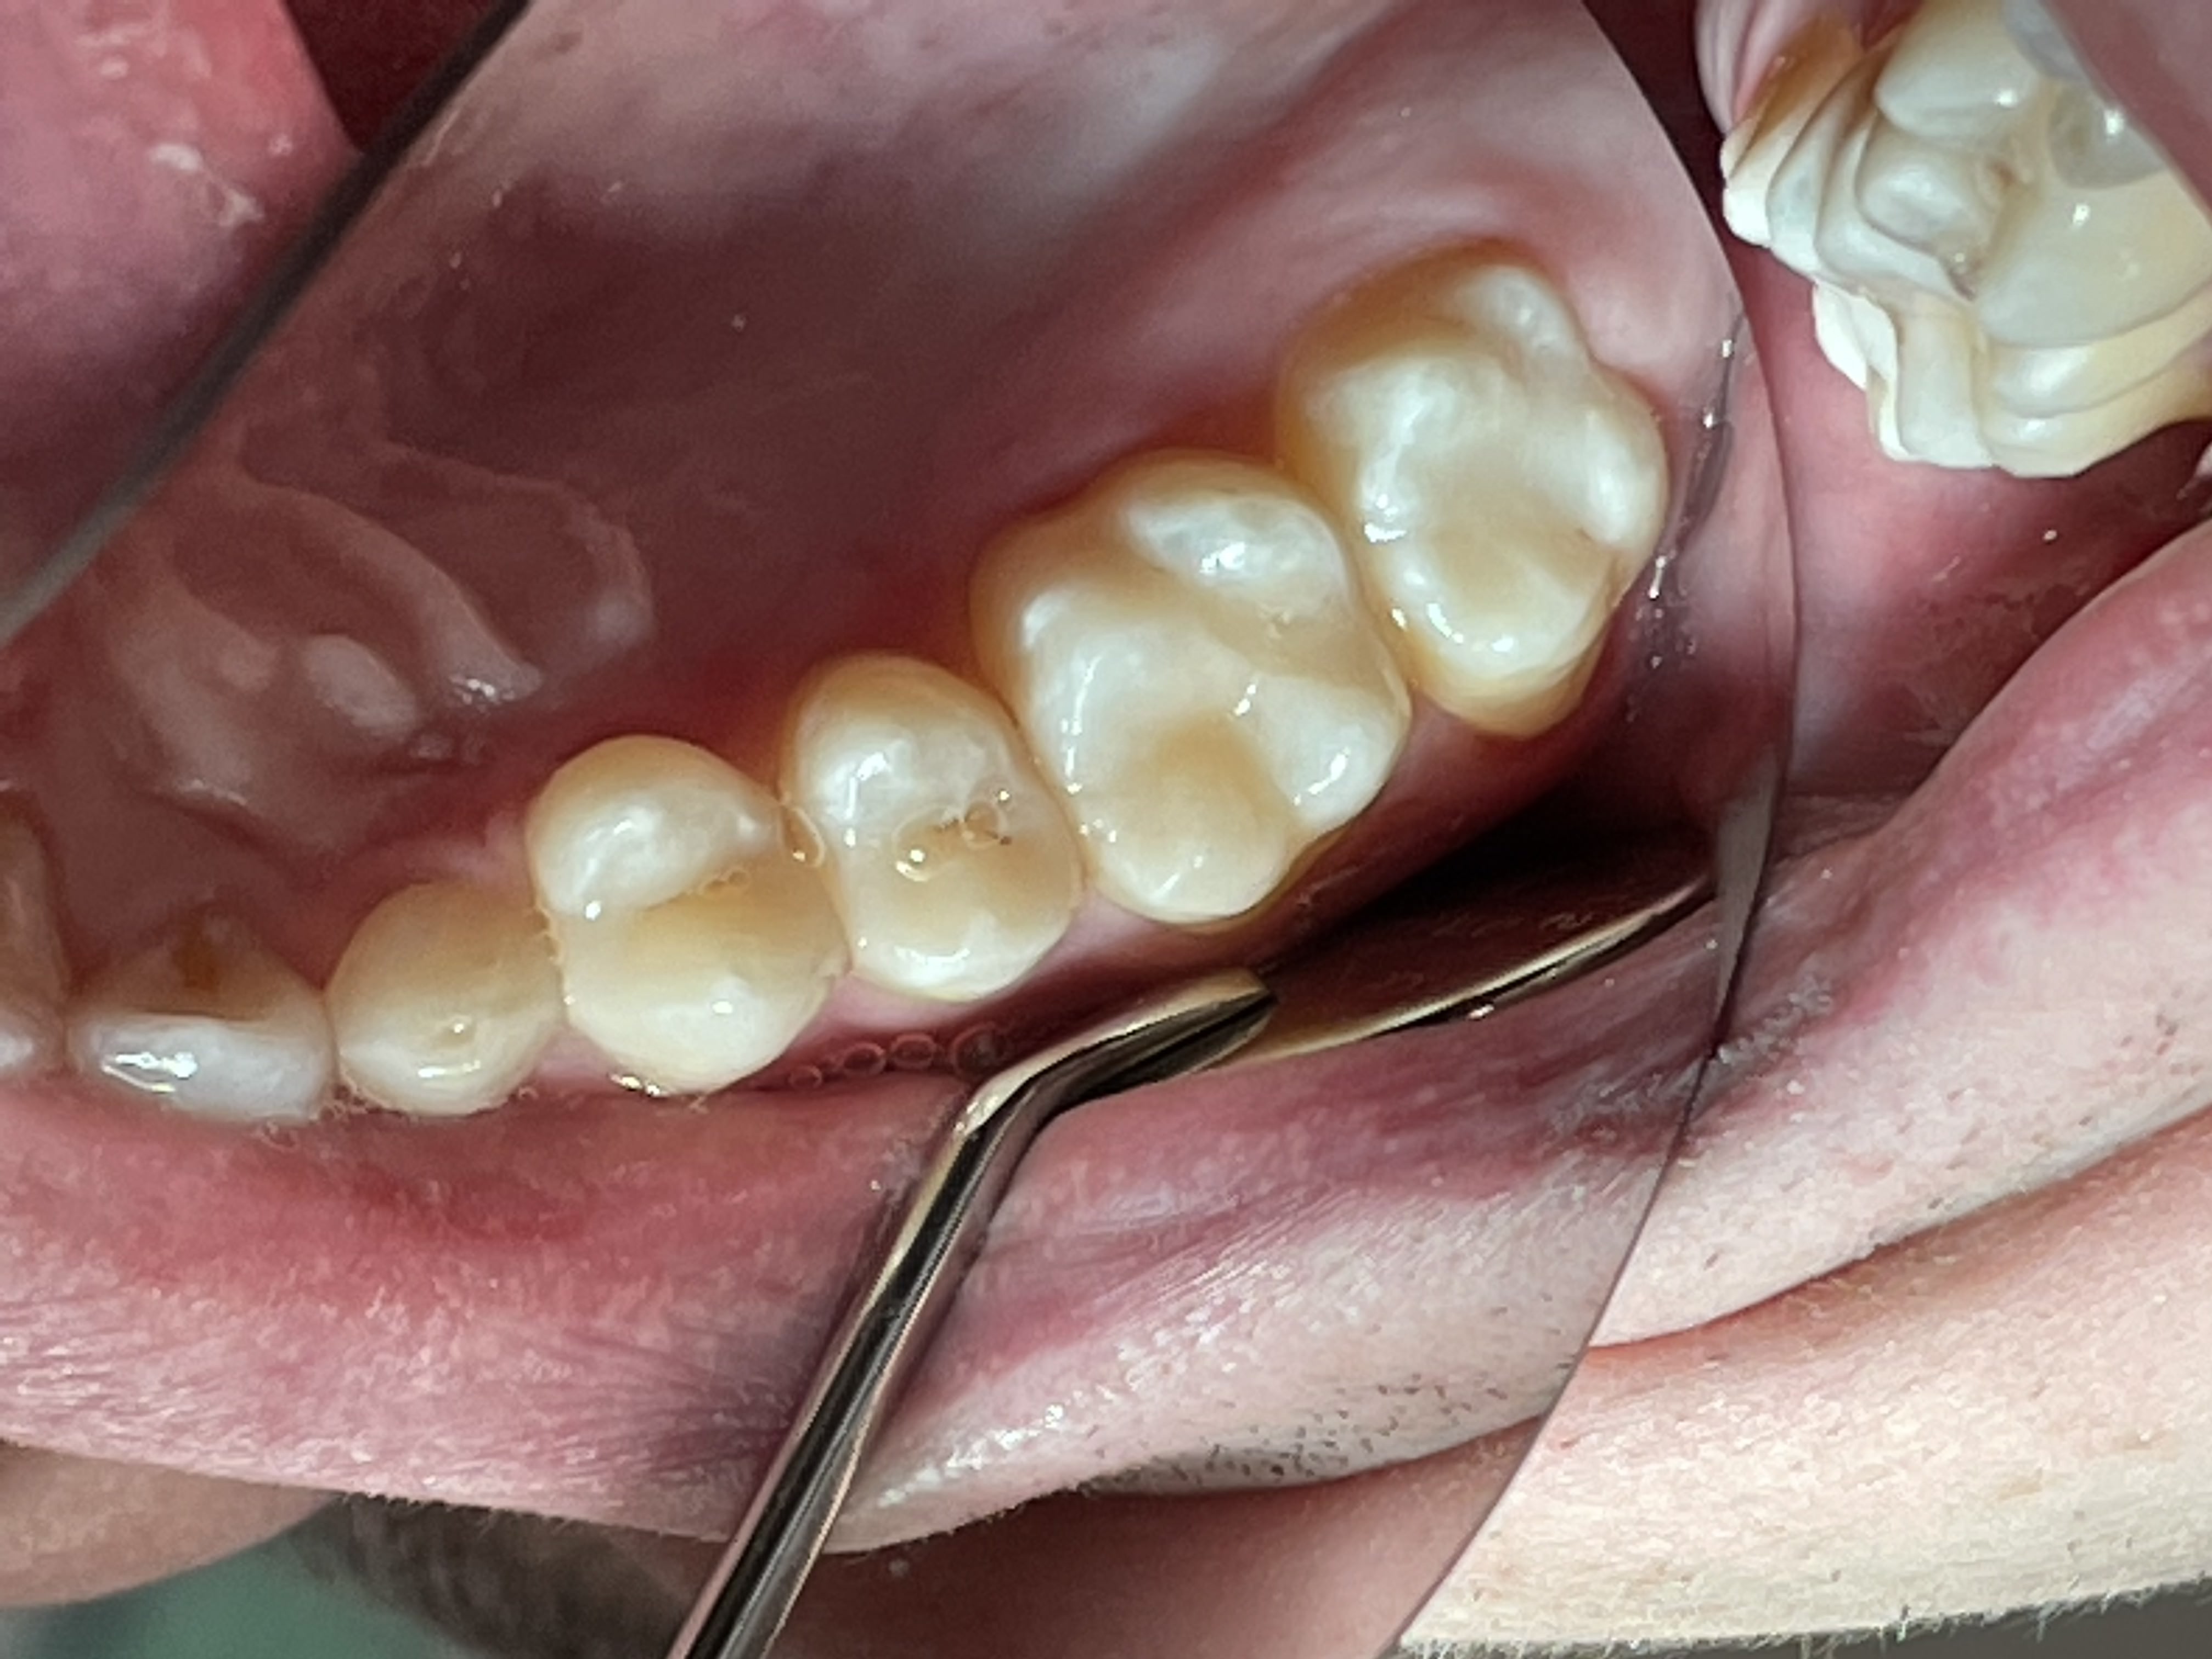

В данной работе на фото достигнута глубина полимеризации микрогибридного Японского композита при помощи диодных, поливалентных фотополимеризаторов без нагревания.

6 этап - Наслоение композита, техника гиперхроматичемкой композитной реставрации жевательных зубов.